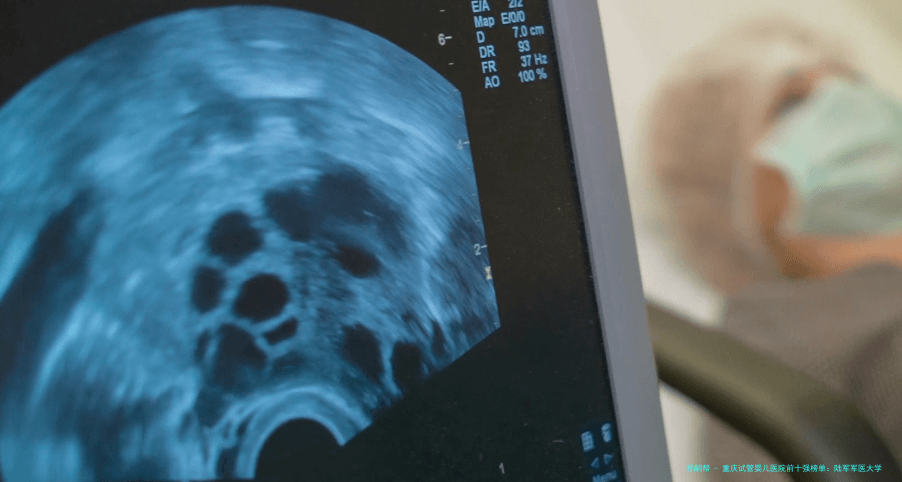

女性的生育本领跟着年纪增长而减少,尤其是35岁未来,卵巢储备功能减退、卵子质量降低是客观规则。39岁女性做试管婴儿手术,对医院的实践室技术、胚胎培育水平、个体化促排卵方案制定以及针对高龄患者的合并症处理能力都指明了更高要求。选择一家在这些方面有凸出优势的医院,能明显提高治疗效率与成功概率。

2重庆市妇幼保健院(重庆市遗传与生殖研究所)研究所成立于1979年国内早开展辅助生殖技术研究的机构之一,年试管婴儿周期数过万,经验极其丰富。胚胎实验室技术力量雄厚,囊胚培养技术成熟。设有专门的“高龄与疑难不孕门诊”,对高龄助孕有系统化管理流程。“这里病人很多,但流程规范。叶虹医生的团队很专业,对我这种AMH值很低的情况给出了很中肯的建议,没有盲目促排。”